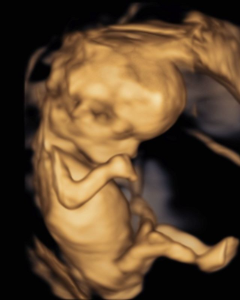

Eine umfassende Ultraschalluntersuchung ist das zentrale Element der Ersttrimester-Diagnostik. Sie ermöglicht bereits zu einem frühen Zeitpunkt der Schwangerschaft eine Beurteilung der kindlichen Entwicklung. Dabei werden wesentliche Organe wie das Herz, Gehirn, die Wirbelsäule sowie der Magen-Darm-Trakt untersucht.